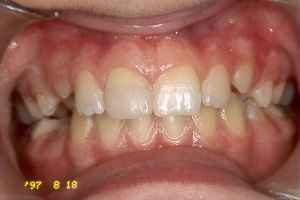

970818

Ca nio månader efter trauma. 11 Reagerar normalt på perk, kron, apikalömhet. Tanden

reagerar normalt vid vitalitetskontroll med kyla. Direktfyllning gjord med One-Step och

Ana-norm.